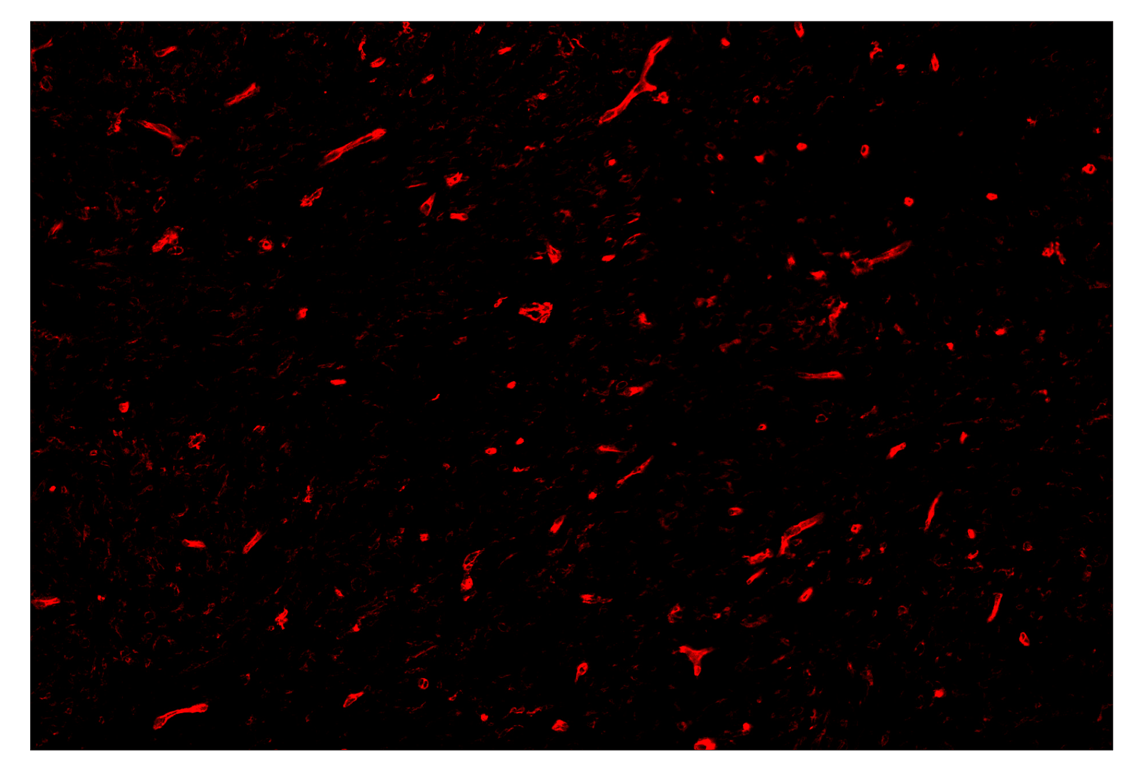

SignalStar™ multiplex immunohistochemical analysis of paraffin-embedded human gastrointestinal stromal tumor using CD141/Thrombomodulin (E7Y9P) & CO-0088-647 SignalStar™ Oligo-Antibody Pair #20811 (red). All fluorophores have been assigned a pseudocolor, as indicated. Staining was performed on the BOND RX autostainer by Leica Biosystems.

Immunohistochemistry Image 4: CD141/Thrombomodulin (E7Y9P) & CO-0088-647 SignalStar<sup>™</sup> Oligo-Antibody Pair